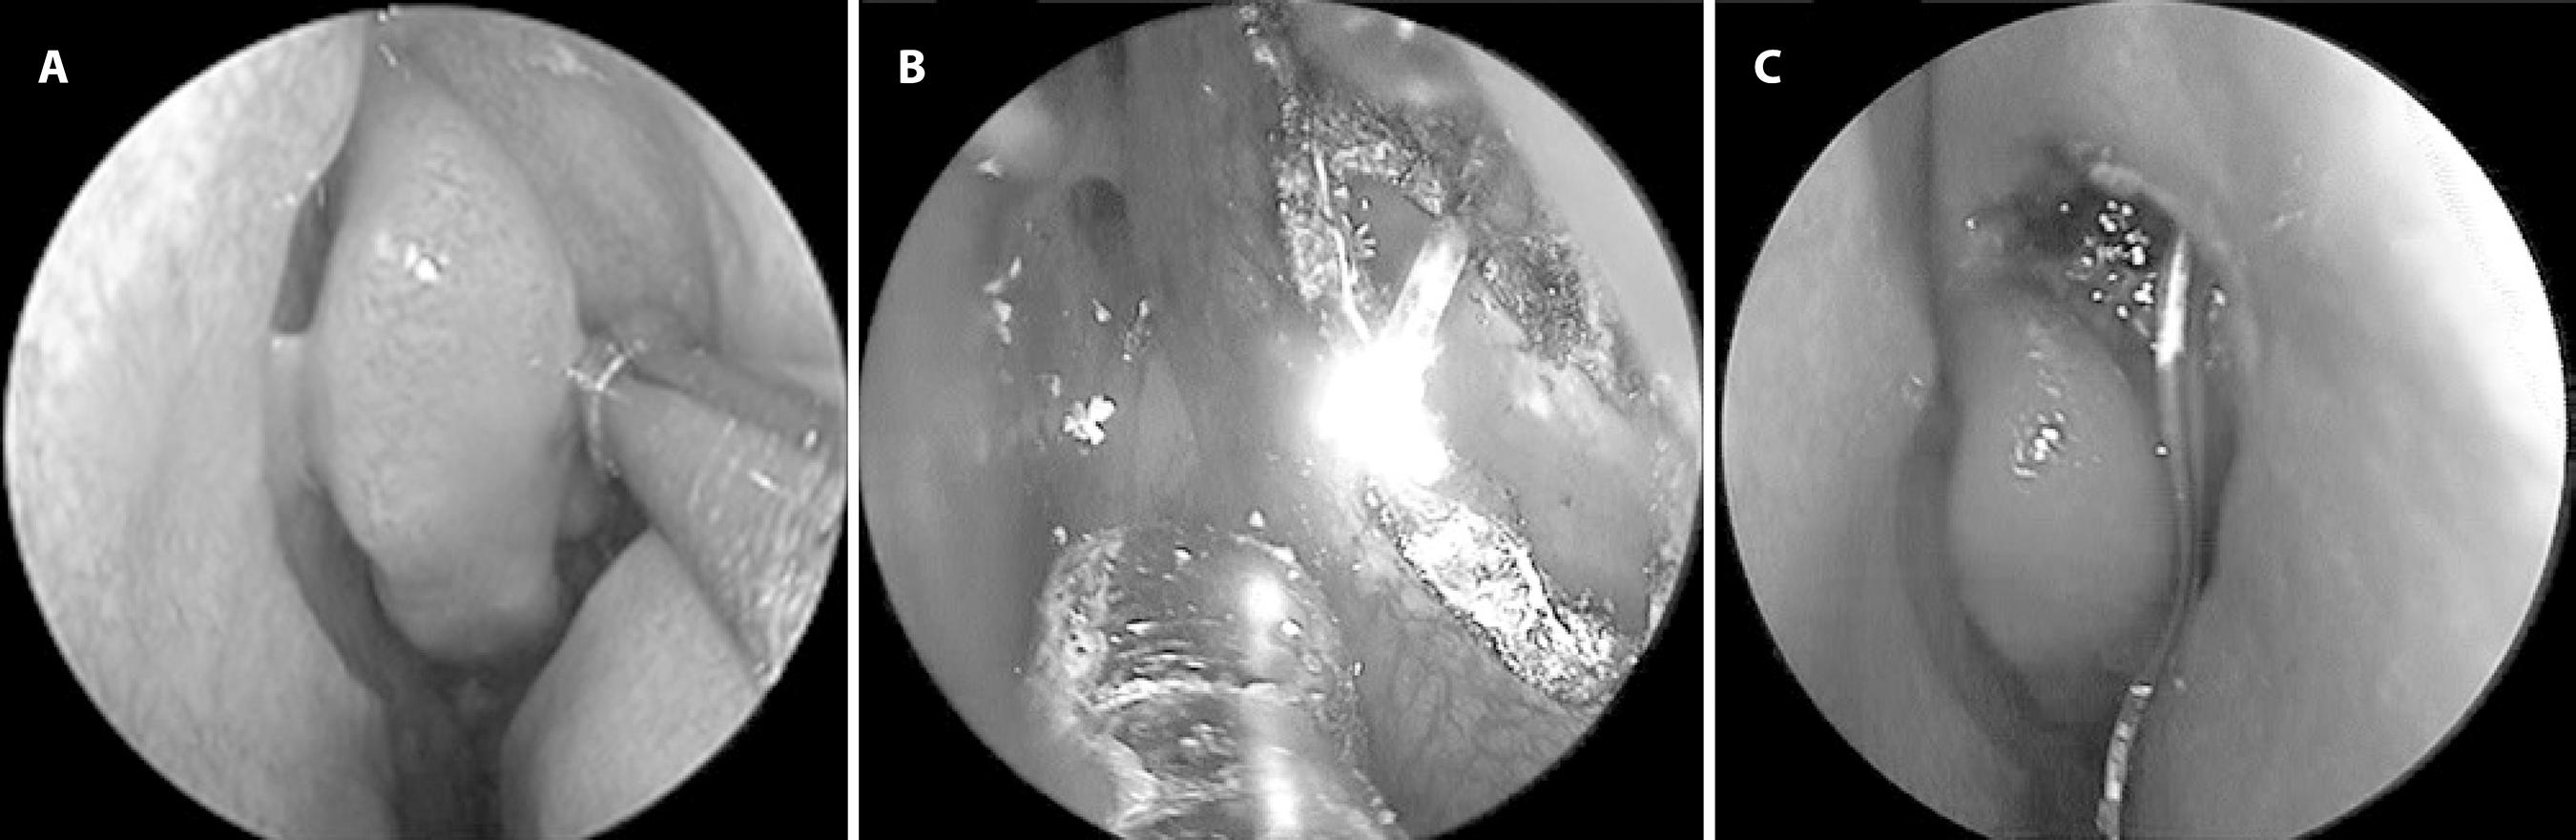

One hour before the surgical intervention, a mixture of 10% xylocaine (Xylocaine pump spray 10%; Astra Zeneca, Istanbul, Turkey) and adrenaline- (Adrenalin 0.5 mg; Osel, Istanbul, Turkey) soaked cotton plugs were inserted into the nasal cavity. The operations were conducted with a transcanalicular 940-nm diode laser (Quanta System, Solbiate Olona, Italy). The inferior and superior puncta were dilated, and a 600-µm laser fiber was passed through the canaliculi up to the sac. A 4-mm, 0-degree, angled, rigid nasal endoscope (Storz, Tübingen, Germany) was introduced into the nasal cavity, and the aiming beam was transmucosally identified (Figure 1 A). The lacrimal bone and nasal mucosa were evaporated using a laser with 8-12 W of power and a 450-ms pause between pulses. The osteotomy diameter sizes were approximately 8 mm vertically and 5 mm horizontally (Figure 1 B). The burned debris around the osteotomy was cleaned with forceps. The total laser energy in joules and operation time were noted. Silicon tubes were inserted into both canaliculi and tightened in the nose (Figure 1 C). The anatomical success was controlled by irrigating the lacrimal system in both canaliculi. Antibiotic-soaked cotton plugs were inserted into the nose and removed after 2 days at the first follow-up visit. The patients were postoperatively treated with mometasone furoate nasal spray (Nasonex; Schering-Plough, Istanbul, Turkey), q 1 h for 1 month, and with 0.1% dexamethasone eye drops (Maxidex; Alcon, Istanbul, Turkey) q 6 h, and 0.3% ofloxacin eye drops (Exocin; Abdi İbrahim, Istanbul, Turkey) q 6 h for 10 days.

Figure 1 A) Red reflex of the laser probe at lacrimal fossa. B) Ostium created by the diode laser. C) A silicon tube passing through the ostium.